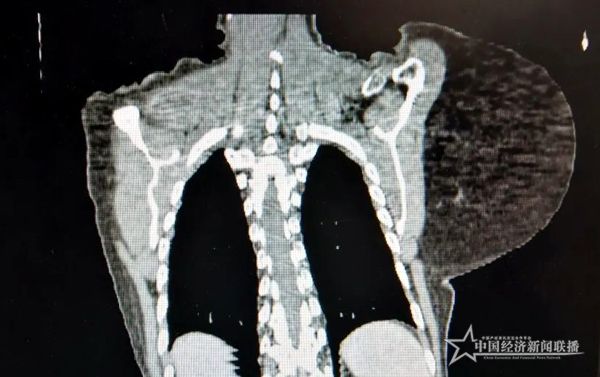

廣西東蘭:六旬老人50年背負(fù)5斤腫瘤成功切除

中經(jīng)聯(lián)播4月26日(覃新強(qiáng) 通訊員 李善威 楊日浪)近日,河池市第三人民醫(yī)院頸胸心血管外科為廣西東蘭的一名六旬老人完整切除長在其背后50年約5斤重的腫瘤。在醫(yī)務(wù)人員的精心治療下,患者已康復(fù)出院回家。

據(jù)了解,患者覃某是河池市東蘭縣花香人,今年63歲,從小身體并沒有出現(xiàn)異常,直到十幾歲的時(shí)候, 左肩膀開始出現(xiàn)黃豆大小的疙瘩,一家人見她整天活蹦亂跳的,沒有人把這事放在心上。直到年齡逐步增大,背后的小疙瘩也隨之變大,慢慢從黃豆模樣長成雞蛋大,雖然腫瘤越長越大,但不疼不癢,且重量較輕,對生活的影響不大,再加之當(dāng)時(shí)家庭經(jīng)濟(jì)比較困難,就醫(yī)意識較為薄弱,就一直拖著,這一拖就是五十年。如今,背后的腫瘤已有足球般大,不僅大又重,成了實(shí)實(shí)在在的累贅,長時(shí)間的重壓,讓她的脊柱側(cè)彎,肩膀和脖子總是酸痛無比,腫瘤還壓迫到神經(jīng),雙手經(jīng)常性出現(xiàn)麻木的狀況。

患者在長期重壓下,脊柱已經(jīng)側(cè)彎

因?yàn)槟[瘤特別大,而且靠近頸部和脊椎,血管神經(jīng)繁多,且老人合并有多種內(nèi)科疾病,經(jīng)過討論,精心為其制定了最佳手術(shù)方案。做足術(shù)前準(zhǔn)備后,該院頸胸心血管外科團(tuán)隊(duì)順利為其施行肩甲部大腫瘤切除術(shù),完整切除約5斤重腫瘤,幫助患者回歸健康人生。